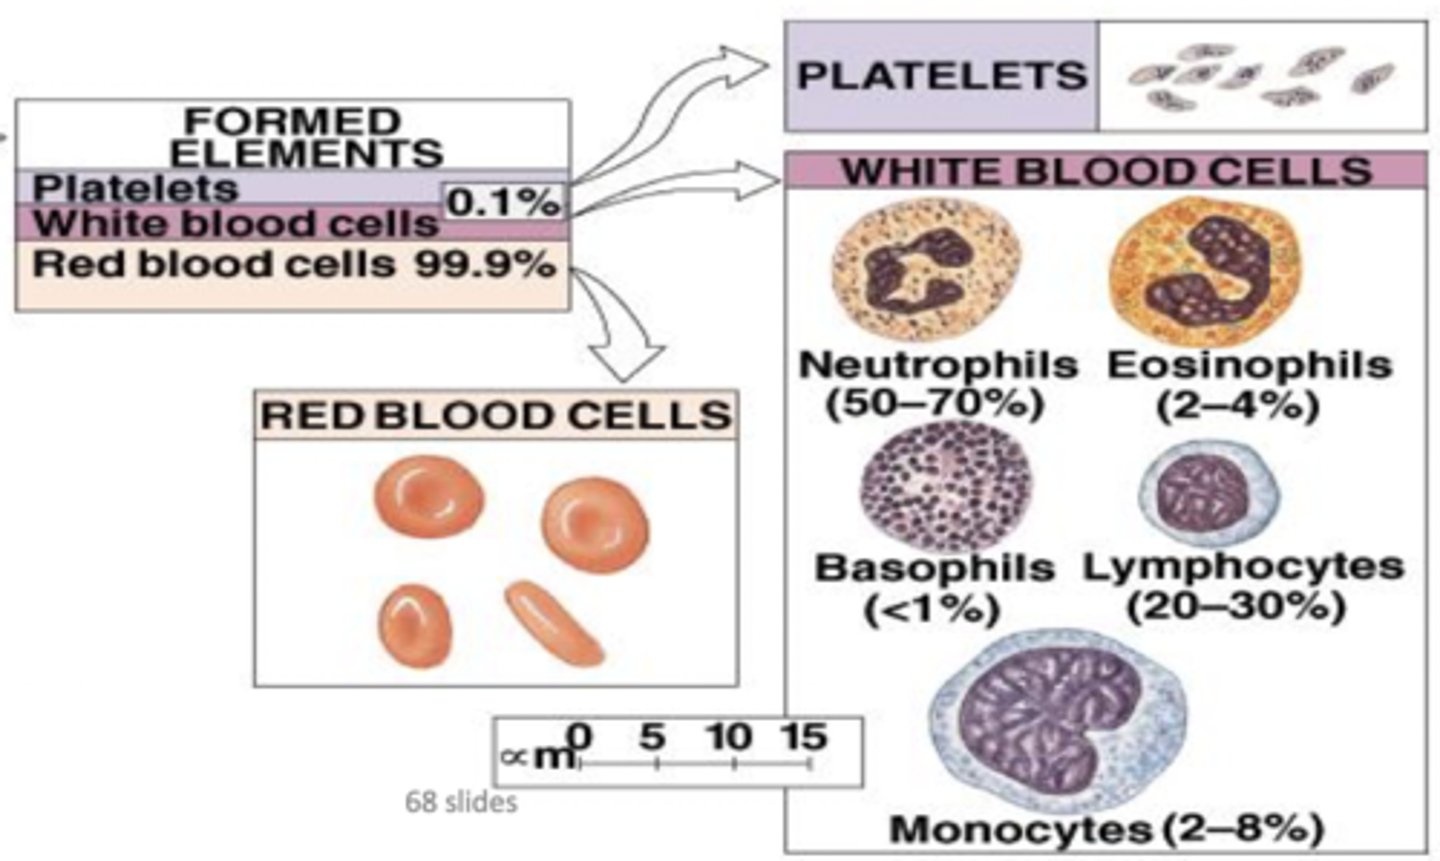

What is the cellular component of blood?

Erythrocytes, leukocytes, thrombocytes (45% of blood)

Leukocytes

White blood cells

Granular leukocytes

Neutrophils, eosinophils, basophils

PHILLED (filled) with granules (enzymes)

Agranular leukocytes

Lymphocytes and monocytes

No granules

What are the two most common leukocytes?

Neutrophils and lymphocytes

Neutrophils

Structure: Nuclei has three or more lobes, granules stain light pink

Function: The most common WBC; fights bacterial infections by engulfing bacteria by phagocytosis

Eosiniphils

Structure: Nuclei has two lobes, granules stain bright red

Function: A WBC that digests and destroys parasitic worms, they also play a role in allergy and immune response

Basophils

Structure: Nuclei is U or S shaped but is obstructed by HUGE blue granules

Function: A WBC that produces histamine --> causing inflammation during an immune response

Monocytes

Structure: Largest WBCs, U shaped nucleus

Function: A large WBC that transform into macrophages to fight off viruses and chronic infections

Lymphocytes

Structure: Has a large, dark purple nucleus that takes up most of the cell volume

Function: B cells make antibodies, T cells fight off viral infections, NK cells